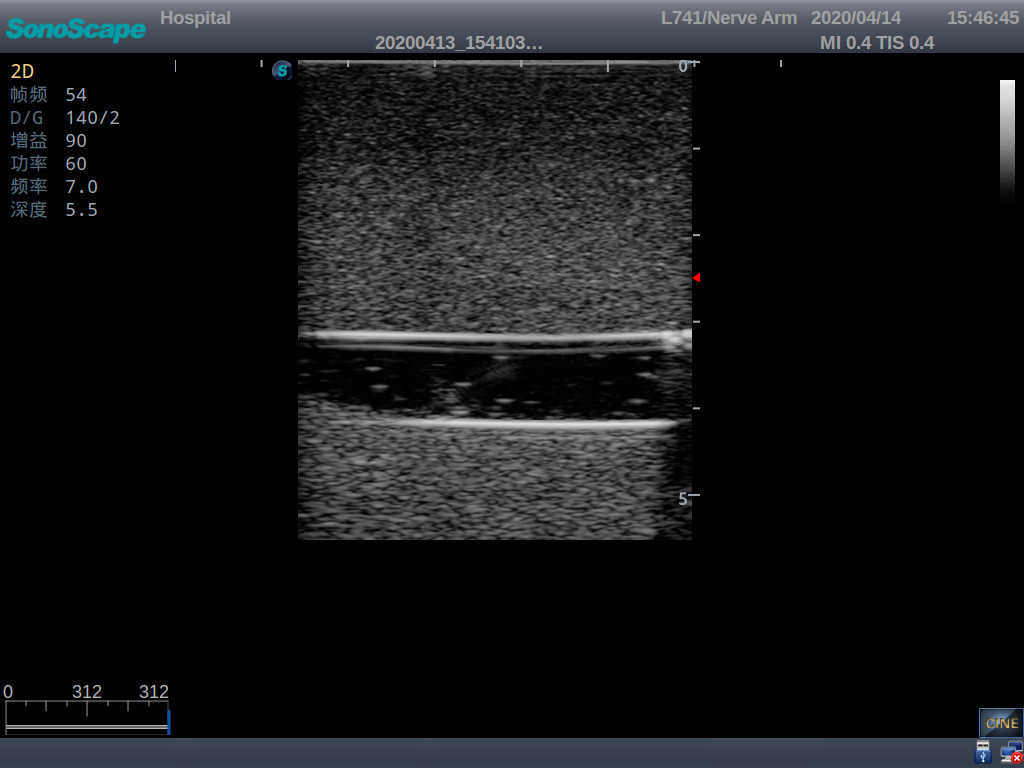

Model TYE1510.1

Outline

It is a model covering up from lobulus auriculae plane to the umbilical plane, and it has anatomical structures like clavicle, rib, sternocleidomastoid, jugular vein and basilic vein.

1)   Made of high molecular polymer ultrasound material, close to the real skin

2)   It can be used by real ultrasound machines

3)   Clear and real images of the tissues and organs (basilic vein and superior vena cava)

5)   Observe the guide wire marches

6)   Detect whether the catheter is properly placed